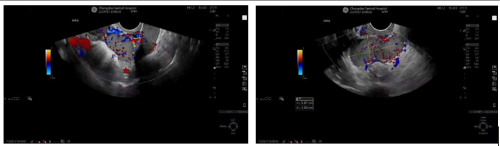

超声显示盆腔内多发肿物,考虑种植脾

11月20日,张芸在香港马会app 健康管理中心接受常规超声检查时,发现了盆腔内多发肿物,且性质较为复杂,无法明确其具体性质,随后,张芸在妇产科三区住院接受进一步诊治。完善盆腔MRI及彩超检查等一系列检查后,结果仍未能准确认定盆底肿物的起源及性质。鉴于张芸病情的特殊性,妇产科三区主任魏馨带领团队深入探讨、广泛查阅相关文献资料,并组织院内多学科会诊,最后诊断盆腔肿物为脾脏组织,免除了张芸遭受手术的痛苦。